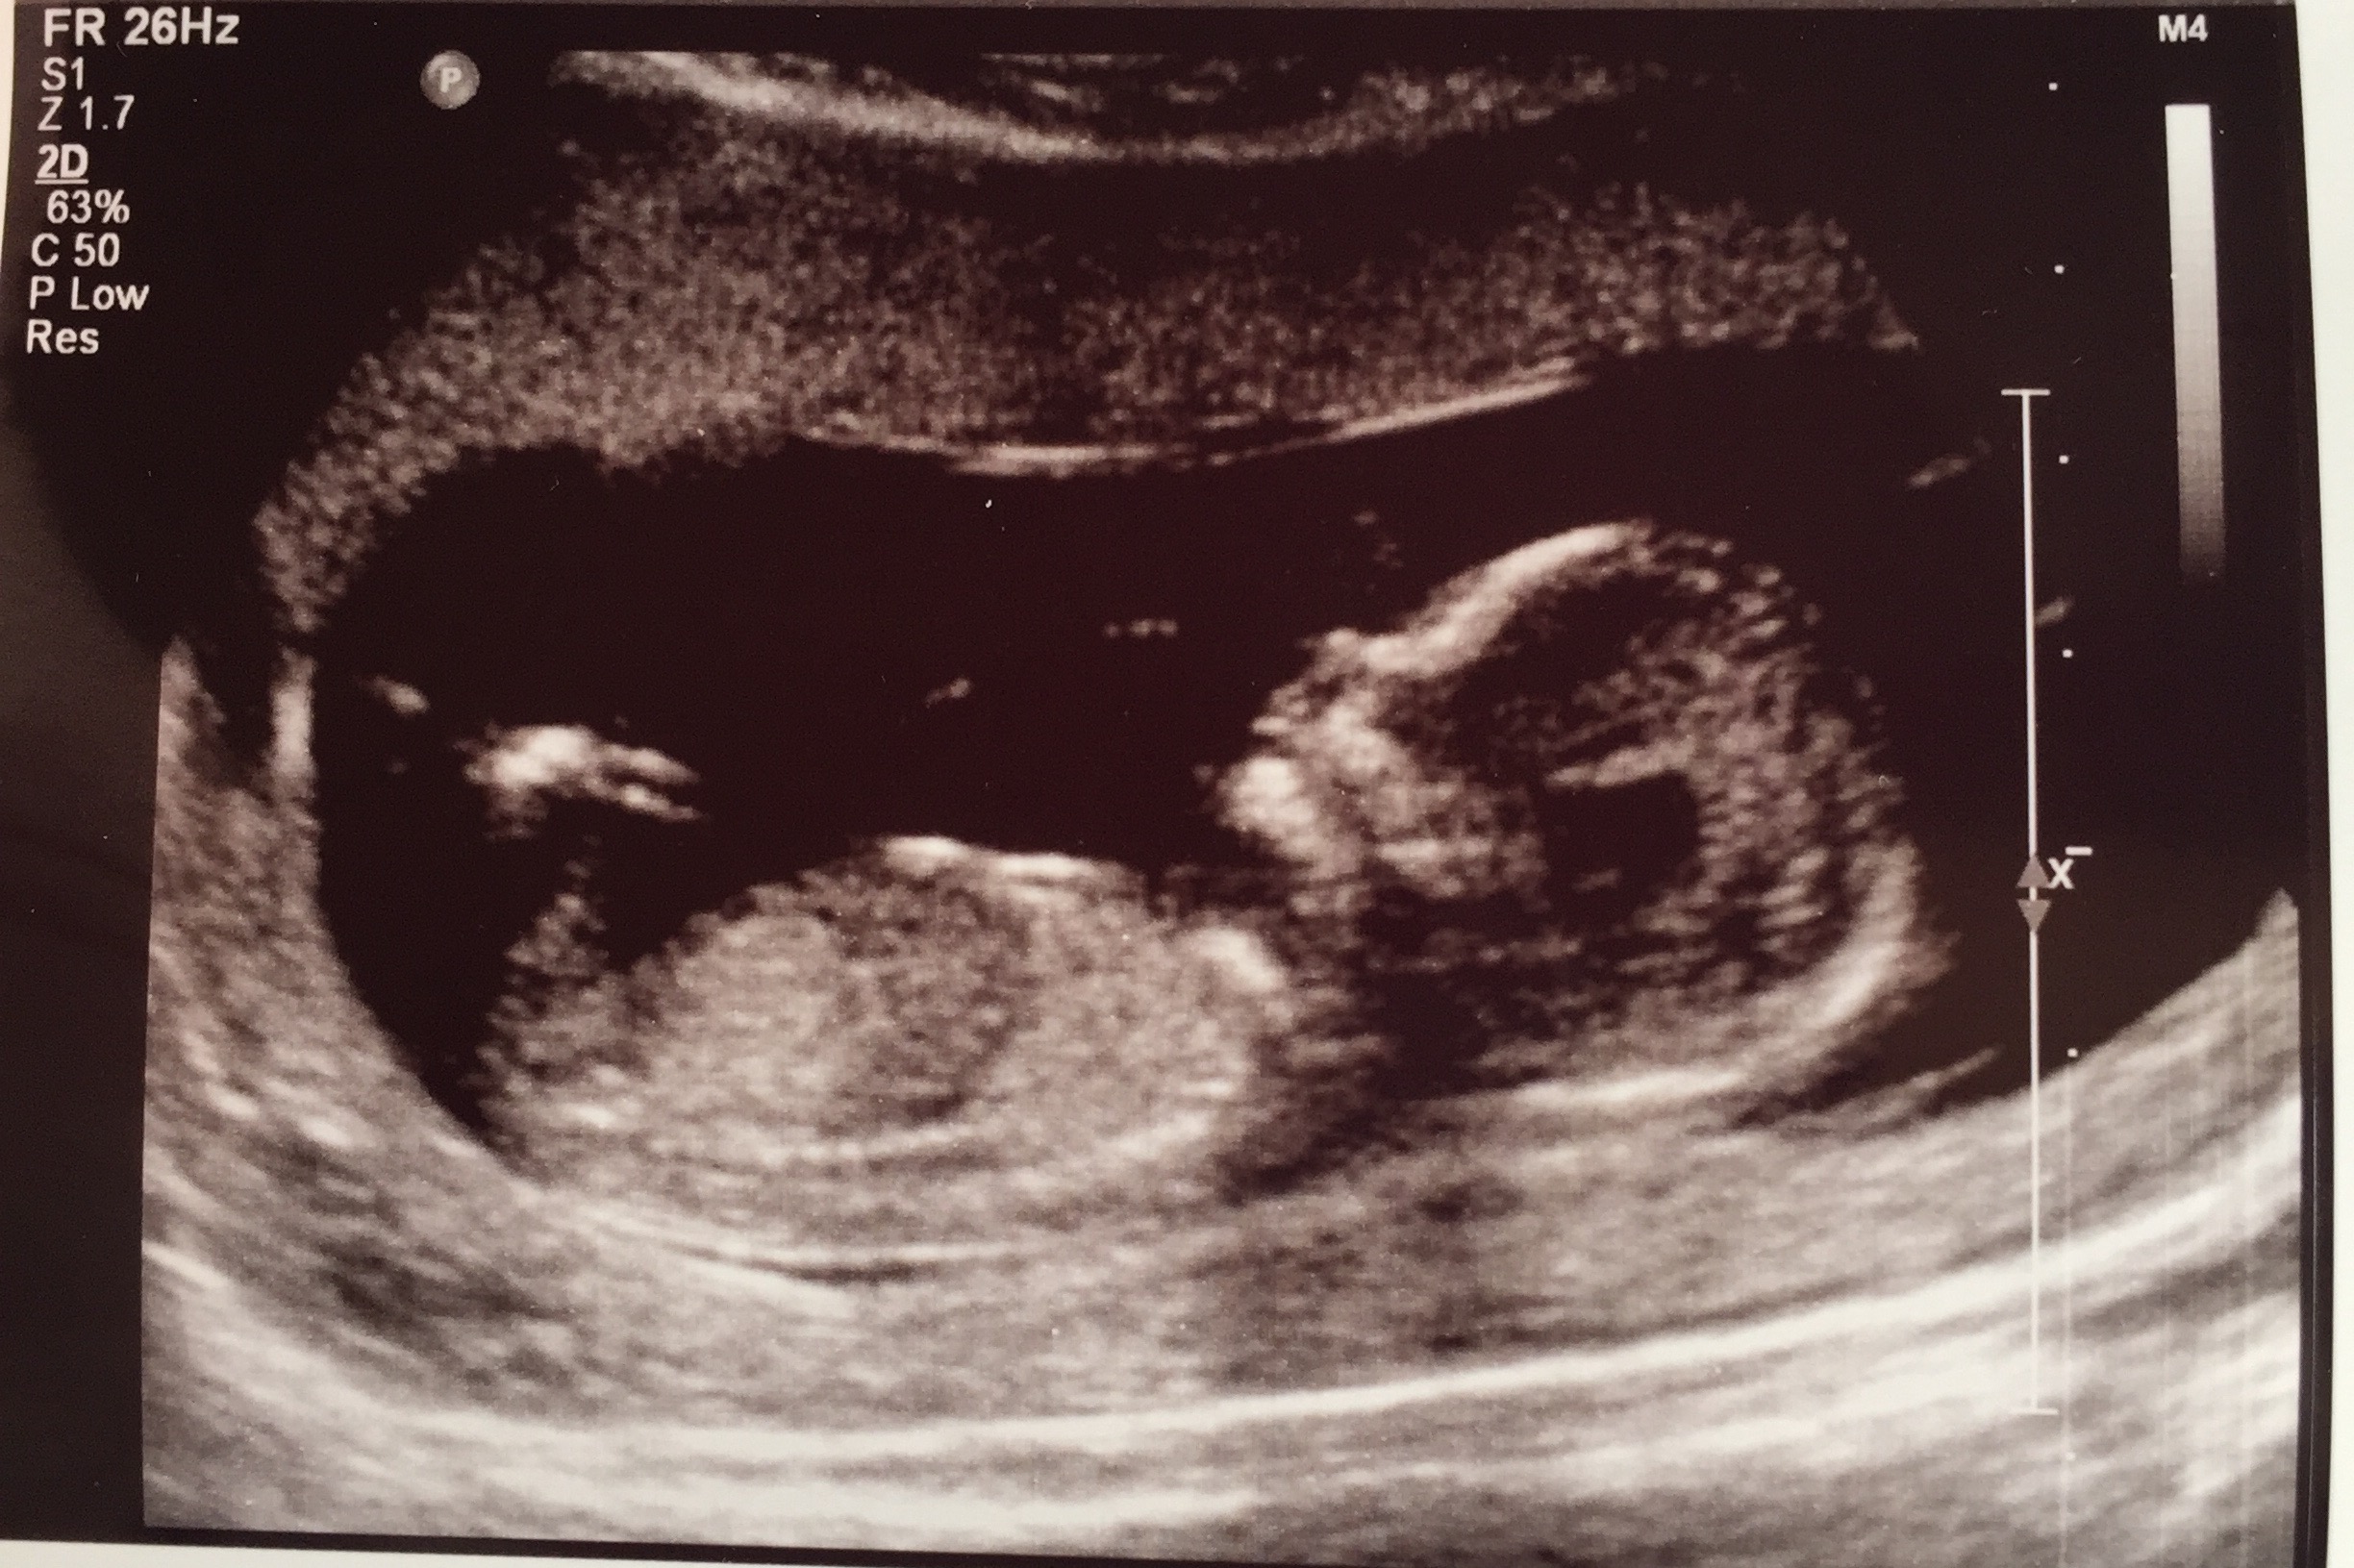

I have been lurking for weeks, waiting to make sure everything was good. After this last ultrasound I am getting more comfortable with embracing this pregnancy. Too scared to jinx anything lol

Hey all! So my US went great today. The measurements all came back perfect. I did get my 1st tri screen as well and they are going to do a baseline 24hr urine just to see. All in all, great visit (even if the MFM specialist is one of my students' mom!)

So my US went great today. The measurements all came back perfect. I did get my 1st tri screen as well and they are going to do a baseline 24hr urine just to see. All in all, great visit (even if the MFM specialist is one of my students' mom!)